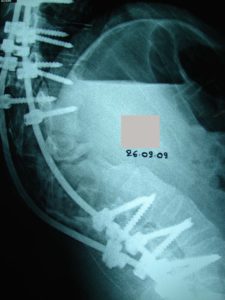

- α

- β

Εικόνα 7 (α,β)

Μετεγχειρητική Μετωπιαία και πλαγία ακτινογραφία της χειρουργηθείσης περιοχής του σκολιωτικού κυρτώματος. Οι διαυχενικοί κοχλίες έχουν τοποθετηθεί εκατέρωθεν του επιπέδου της οστεοτομίας.

Ο ασθενής κινητοποιήθηκε άμεσα την επομένη της επέμβασης και βάδισε ομαλά, εξήλθε δε μετά 4ήμερο χωρίς να φορά κηδεμόνα. Η μετεγχειρητική πορεία ήταν εντός των φυσιολογικών πλαισίων και μετά 30ήμερο άρχισε να έχει ήπιες δραστηριότητες.

Ο τελευταίος κλινικο-ακτινολογικός έλεγχος έγινε 10 μήνες μετά την επέμβαση ο οποίος έδειξε την καλή θέση των υλικών σπονδυλοδεσίας. Ο ασθενής επανήλθε σε πολύ ήπιες δραστηριότητες – όχι χειρωνακτικές- δόθηκαν οδηγίες για προοδευτική αύξηση των δραστηριοτήτων το επόμενο εξάμηνο όπου και θα επανεξετασθεί η γενικότερη κατάστασή του.